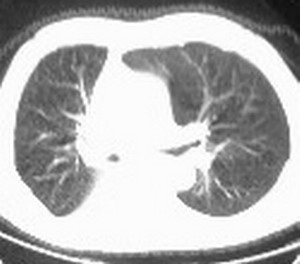

右肺下叶支气管闭塞,伴下叶实变不张。建议增强及纤支镜。

右肺下野后部均匀低密度影,边缘锐利,前缘外突(不支持肺不张),纵隔内未见明显肿大淋巴结,右下肺门结构显示欠清,临床资料太过简单,考虑右侧后胸部包裹性积液。其他待排。建议密切结合临床其他检查。

右肺下叶未发育,并包裹性胸腔积液